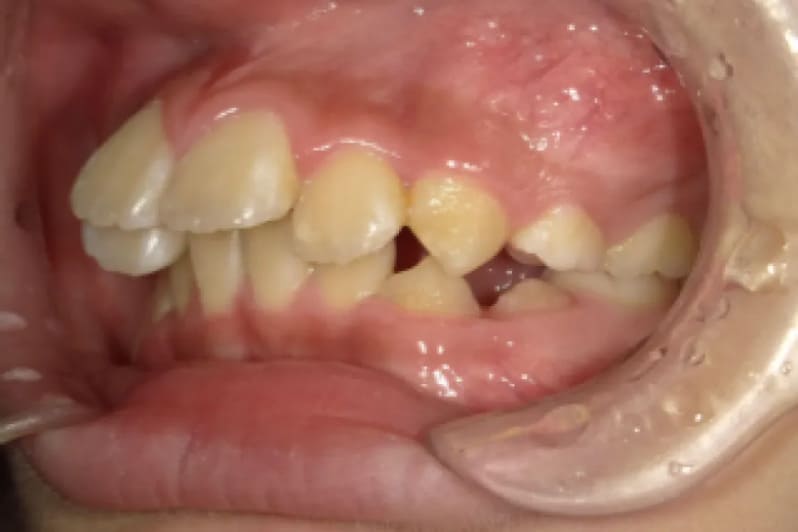

| Before | ![]() |

| 性別 | 女性 |

| 年齢 | 10代 |

| 治療費用 | 902,000円 |

| 治療期間 | 2年11ヶ月 |

| 治療内容 | マウスピース矯正 |

| リスク 副作用 |

矯正治療の一般的なリスクといたしましては、治療中のお痛み・歯根吸収・歯肉退縮・治療後の後戻りなどが生じる可能性があります。矯正治療は始めると、元の状態に戻すのが難しいことがあります。 |